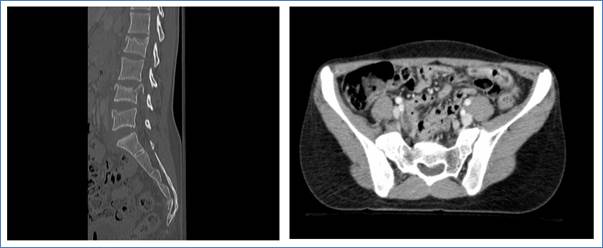

A 25 years old female, Indonesian domestic worker had fallen off the 2nd floor of her flat and suffered polytrauma. Injuries sustained include burst fracture of L2-4 vertebrae, sacral comminuted fracture (S3-5), an antero-superiorly displaced L5 vertebral body, along with right basal skull fracture, right mandibular fracture and right calcaneal fracture. No saddle anesthesia or sensory-motor deficits were recorded on admission. She underwent posterior instrumented fusion T11-Pelvis with decompression Laminectomy at L4.

Figure 2. 25-years-old female with polytrauma involving S3-5 sacral vertebral fractures (Denis zone 2)

Source of Figures 1a,b and Figures 2a, b: Department of Rehabilitation Medicine, Changi General Hospital, 2 Simei street 3 Singapore 529889.